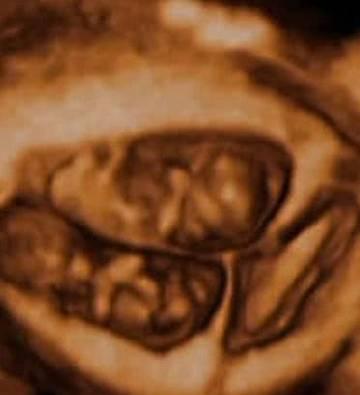

龙凤胎图片(子宫里:双胞胎、三胞胎和四胞胎究竟什么样?八图带你一次看清楚)怀孕的准妈妈们总是幸福而谨慎的。一方面,肚子里的小生命带给准妈妈们母爱的幸福光辉,而另一方面,准妈妈们也时时刻刻都为自己的宝宝操心。害怕自己不够小心谨慎伤到宝宝,害怕宝宝营养不足而发育不良...[详细]